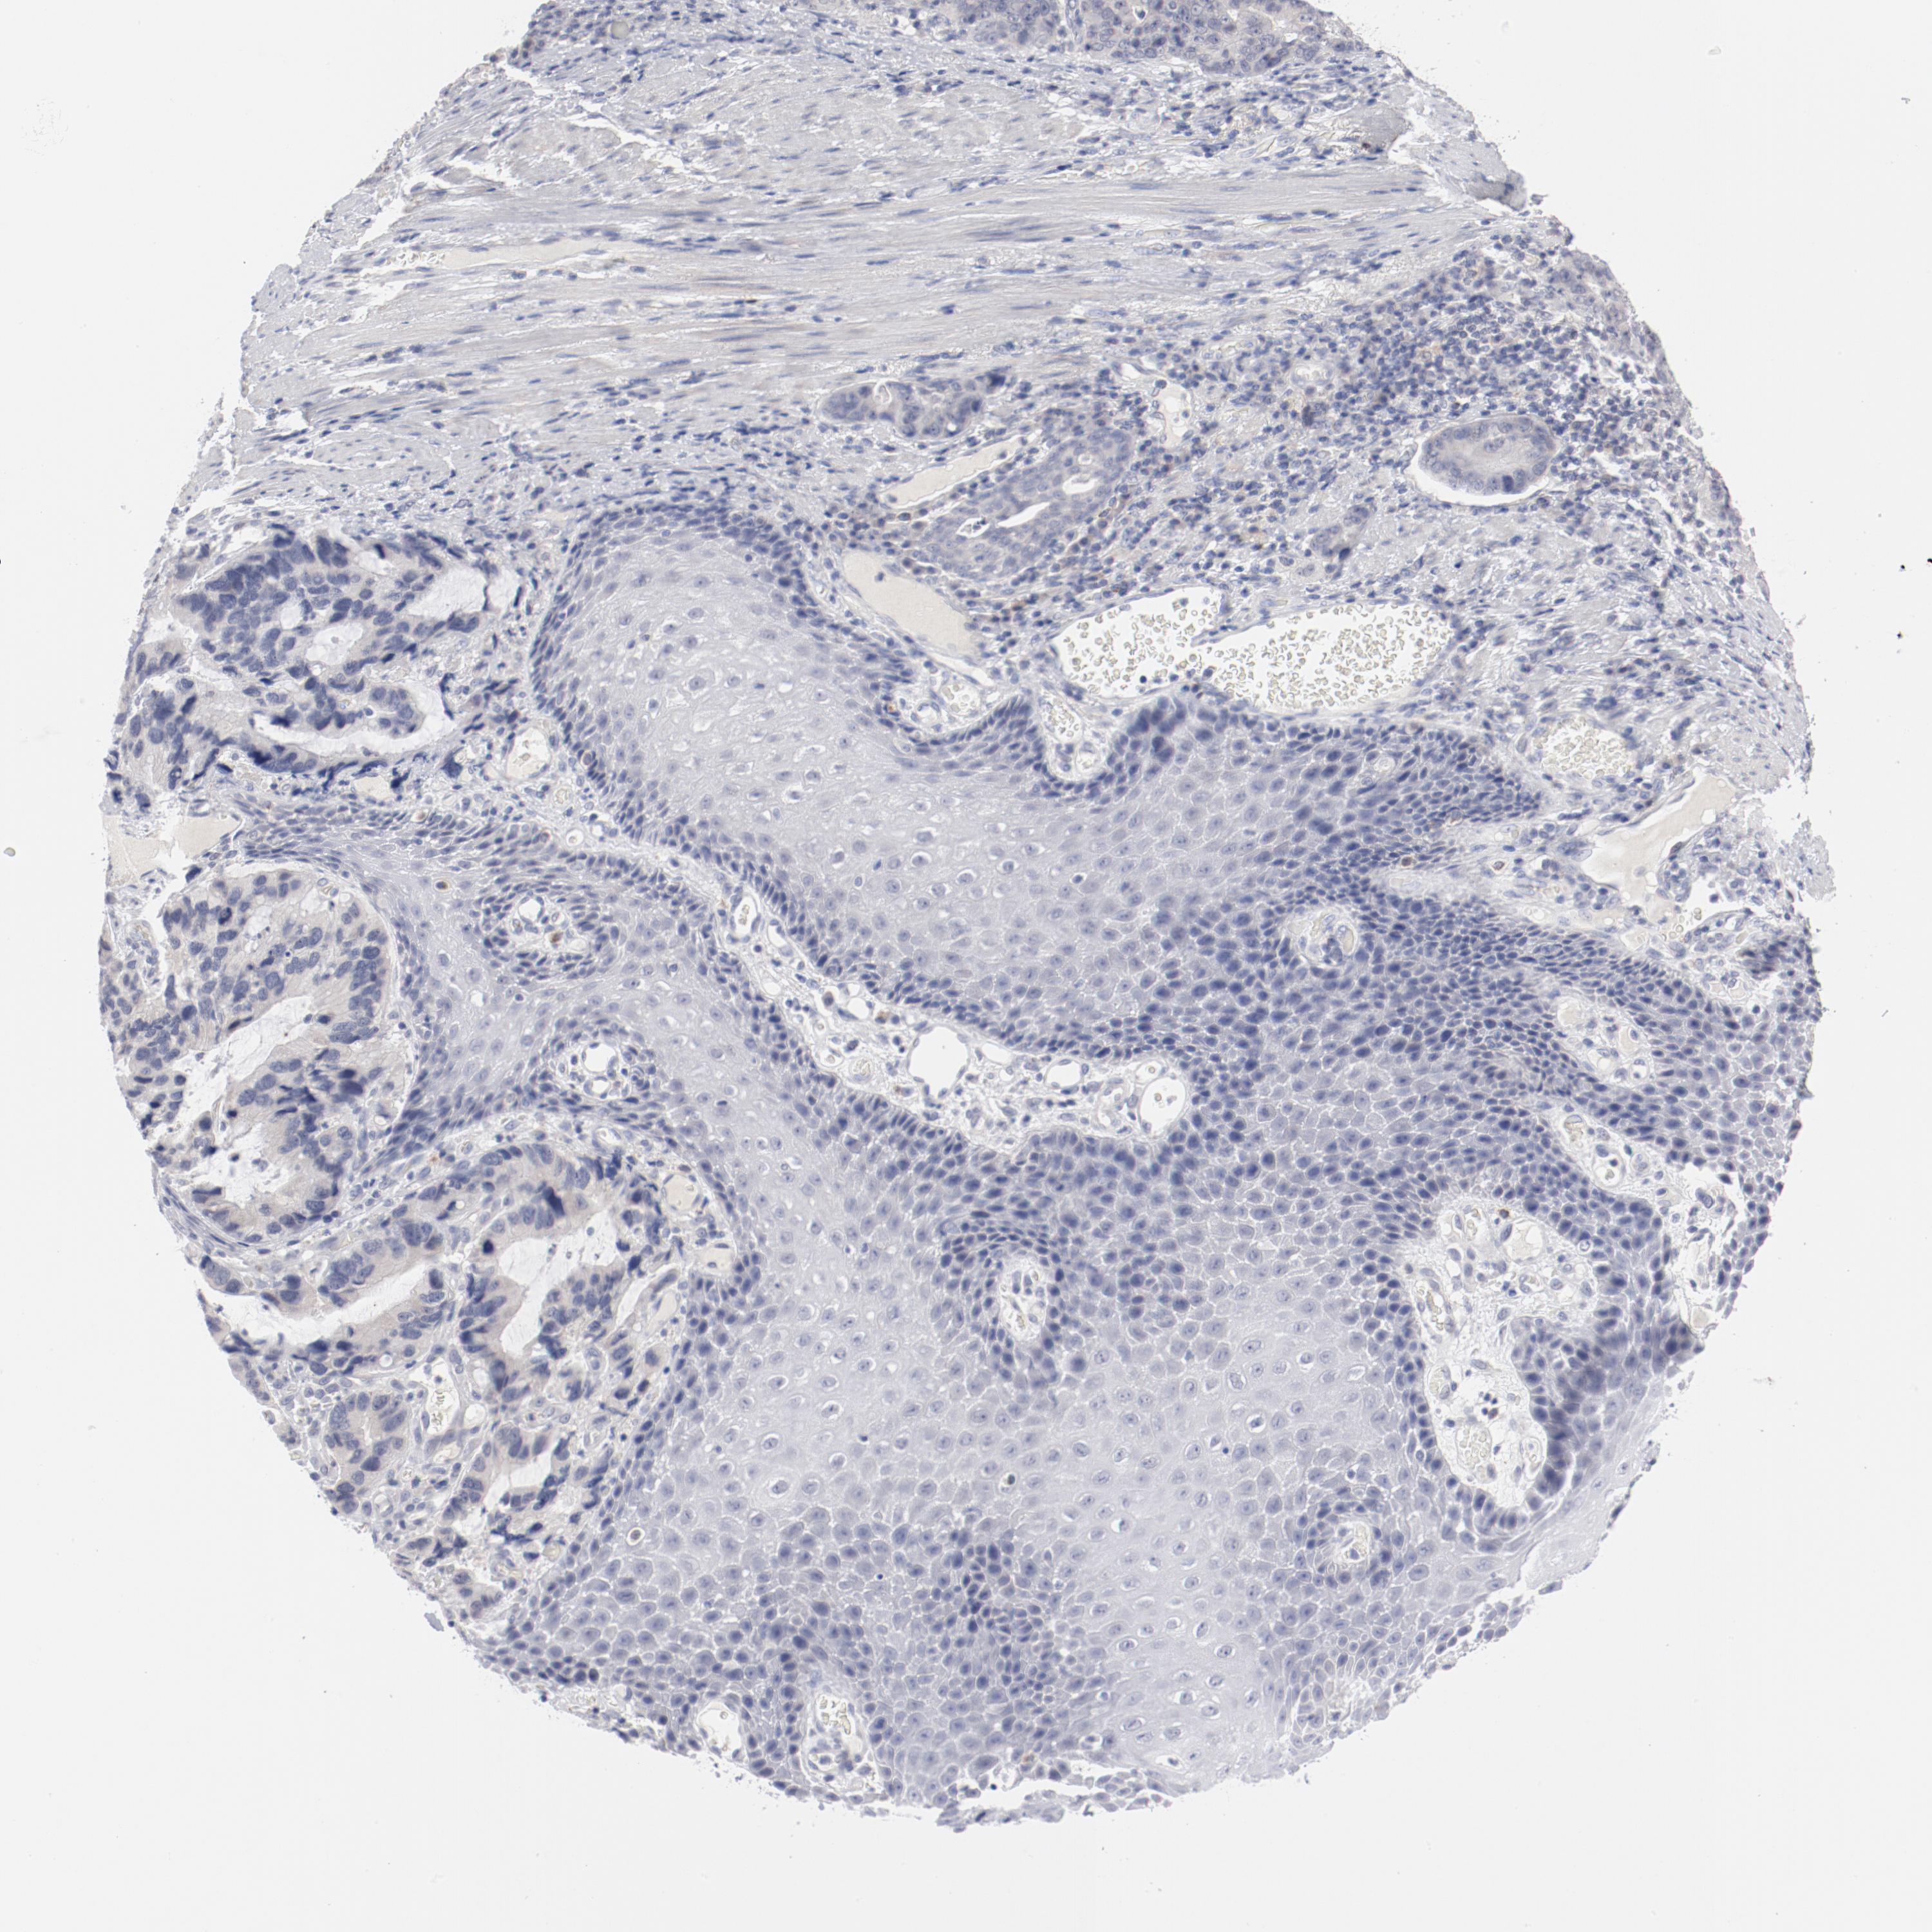

STOMACH CANCER - Protein expressioni

A mouse-over function shows sample information and annotation data. Click on an image to view it in a full screen mode. Samples can be filtered based on level of antibody staining by selecting one or several of the following categories: high, medium, low and not detected. The assay and annotation is described here.

Note that samples used for immunohistochemistry by the Human Protein Atlas do not correspond to samples in the TCGA dataset.

Antibody stainingi

Antibody staining in the annotated cell types in the current human tissue is reported as not detected, low, medium, or high, based on conventional immunohistochemistry profiling in selected tissues. This score is based on the combination of the staining intensity and fraction of stained cells.

Each image is clickable and will lead to virtual microscopy that enables deeper exploration of all samples and also displays staining intensity scores, fraction scores and subcellular localization as well as patient and tissue information for each sample.

Antibody CAB003685

Staining

High

Medium

Low

Not detected

Intensity

Strong

Moderate

Weak

Negative

Quantity

>75%

75%-25%

<25%

None

Location

Nuclear

Cytoplasmic/membranous

Cytoplasmic/membranous,nuclear

Adenocarcinoma, NOS